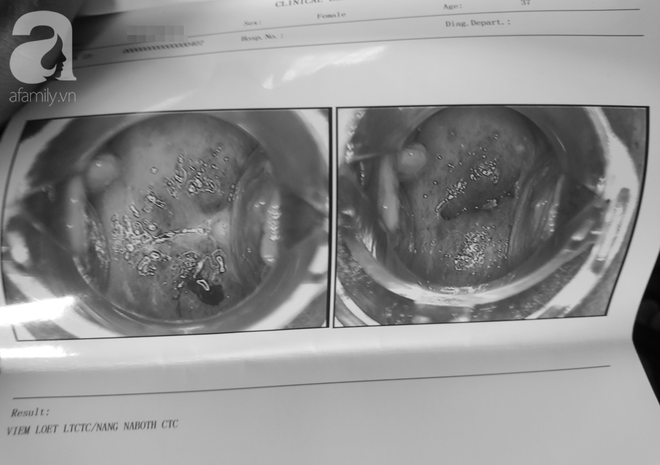

Chẩn đoán viêm loét tử cung kèm nang cổ tử cung của bệnh nhân A. tại phòng khám Royal.

Hình ảnh soi tử cung của bệnh nhân kèm theo chẩn đoán viêm loét tử cung lộ tuyến.